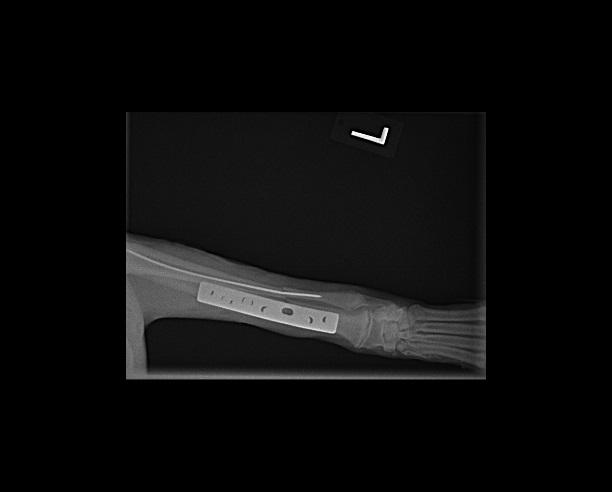

His radius and ulna were both fractured, the two bones that correspond with our forearm. The best repair for this type of fracture is a metal plate. Drs. Yoder and Coughlin placed a pin down his ulna to align the bones and assist in stabilizing the area. Then they used screws to place a metal plate on his radius to hold the two pieces of bone close together and prevent movement. For the first month Loki wore a splint to help keep everything stable in such an active puppy. In eight weeks he was walking with a slight limp and was getting back to his normal activities.

These images are post surgery checking for appropriate pin placement and alignment of the fracture.